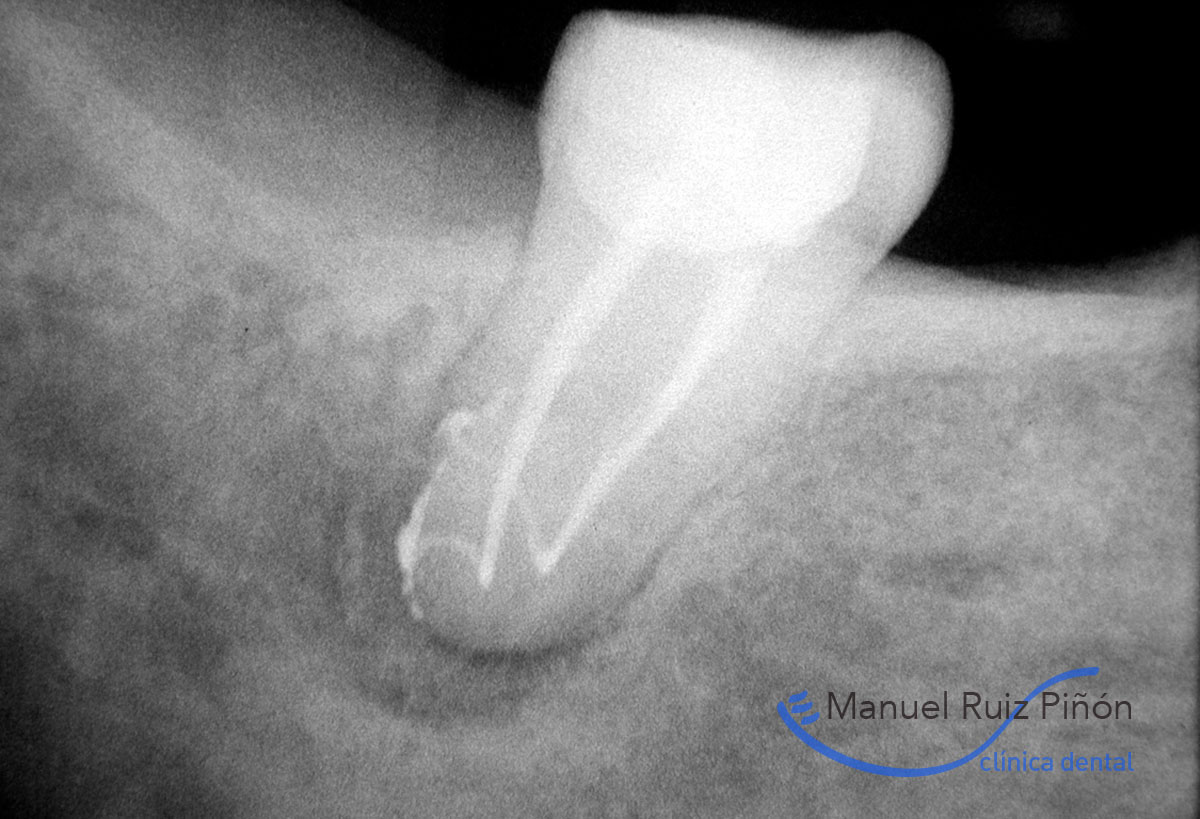

Normalmente los conductos radiculares por donde se dispone la pulpa se ramifican creando en su conjunto lo que denomina un sistema de conductos (1, 2); además no son rectos, y en ocasiones presentan grandes curvaturas que son muy difíciles de limpiar y sellar tridimensionalmente(3-4). Las calcificaciones, i